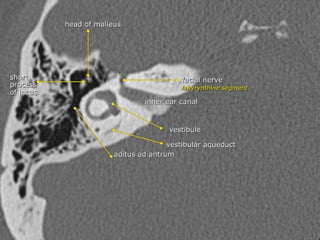

Anterior tympanic level

The TM may be identified as a thin filamentous

structure extending from the scutum superiorly and

coursing parallel to the plane of the long process of the

malleus to attach to the limbus inferiorly.

The head and neck of the malleus can be seen in the

epitympanic space, with the tendon of the tensor

tympani muscle attaching to neck.

The labyrinthine and tympanic segments of the facial

nerve are seen as two lucencies superior to the

cochlea.